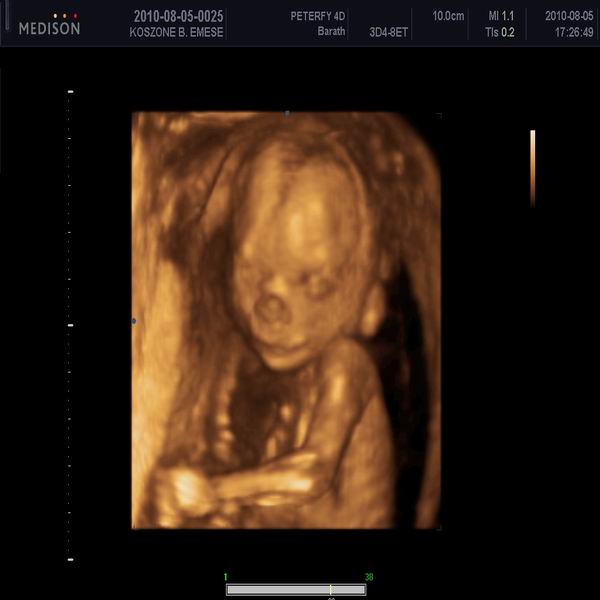

nagyon boldog vagyok!!!!! "A" baba: kisfiúnk 41 mm fejkörfogat és 213 g, fejvégű, "B" baba: a lányunk is 41 mm fejkörtérfogat és 222g. medence végű. mindenük megvan, mindenük ép, ficánkolós a kislány a fiúcska nyugodtabb egyenlőre:) ép szív máj vesék telitett hólyag gyomor bél:)))))